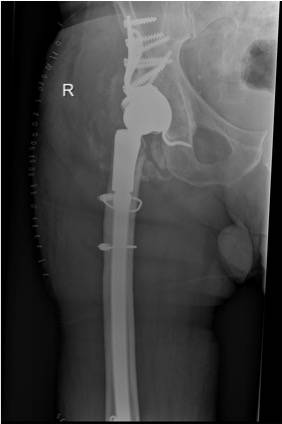

Einer der größeren endoprothetischen Eingriffe: eine Gelenkpfannenrekonstruktion des Hüftgelenks.